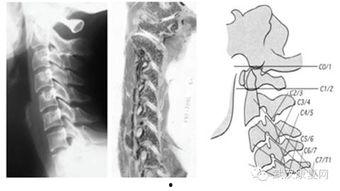

5. 颈椎关节松动技术

颈椎关节是连接头部和身体的重要关节,保持颈椎的健康对我们的生活影响也不小。这个视频教程会教你如何通过关节松动技术,缓解颈椎的疼痛,提高颈椎的稳定性。